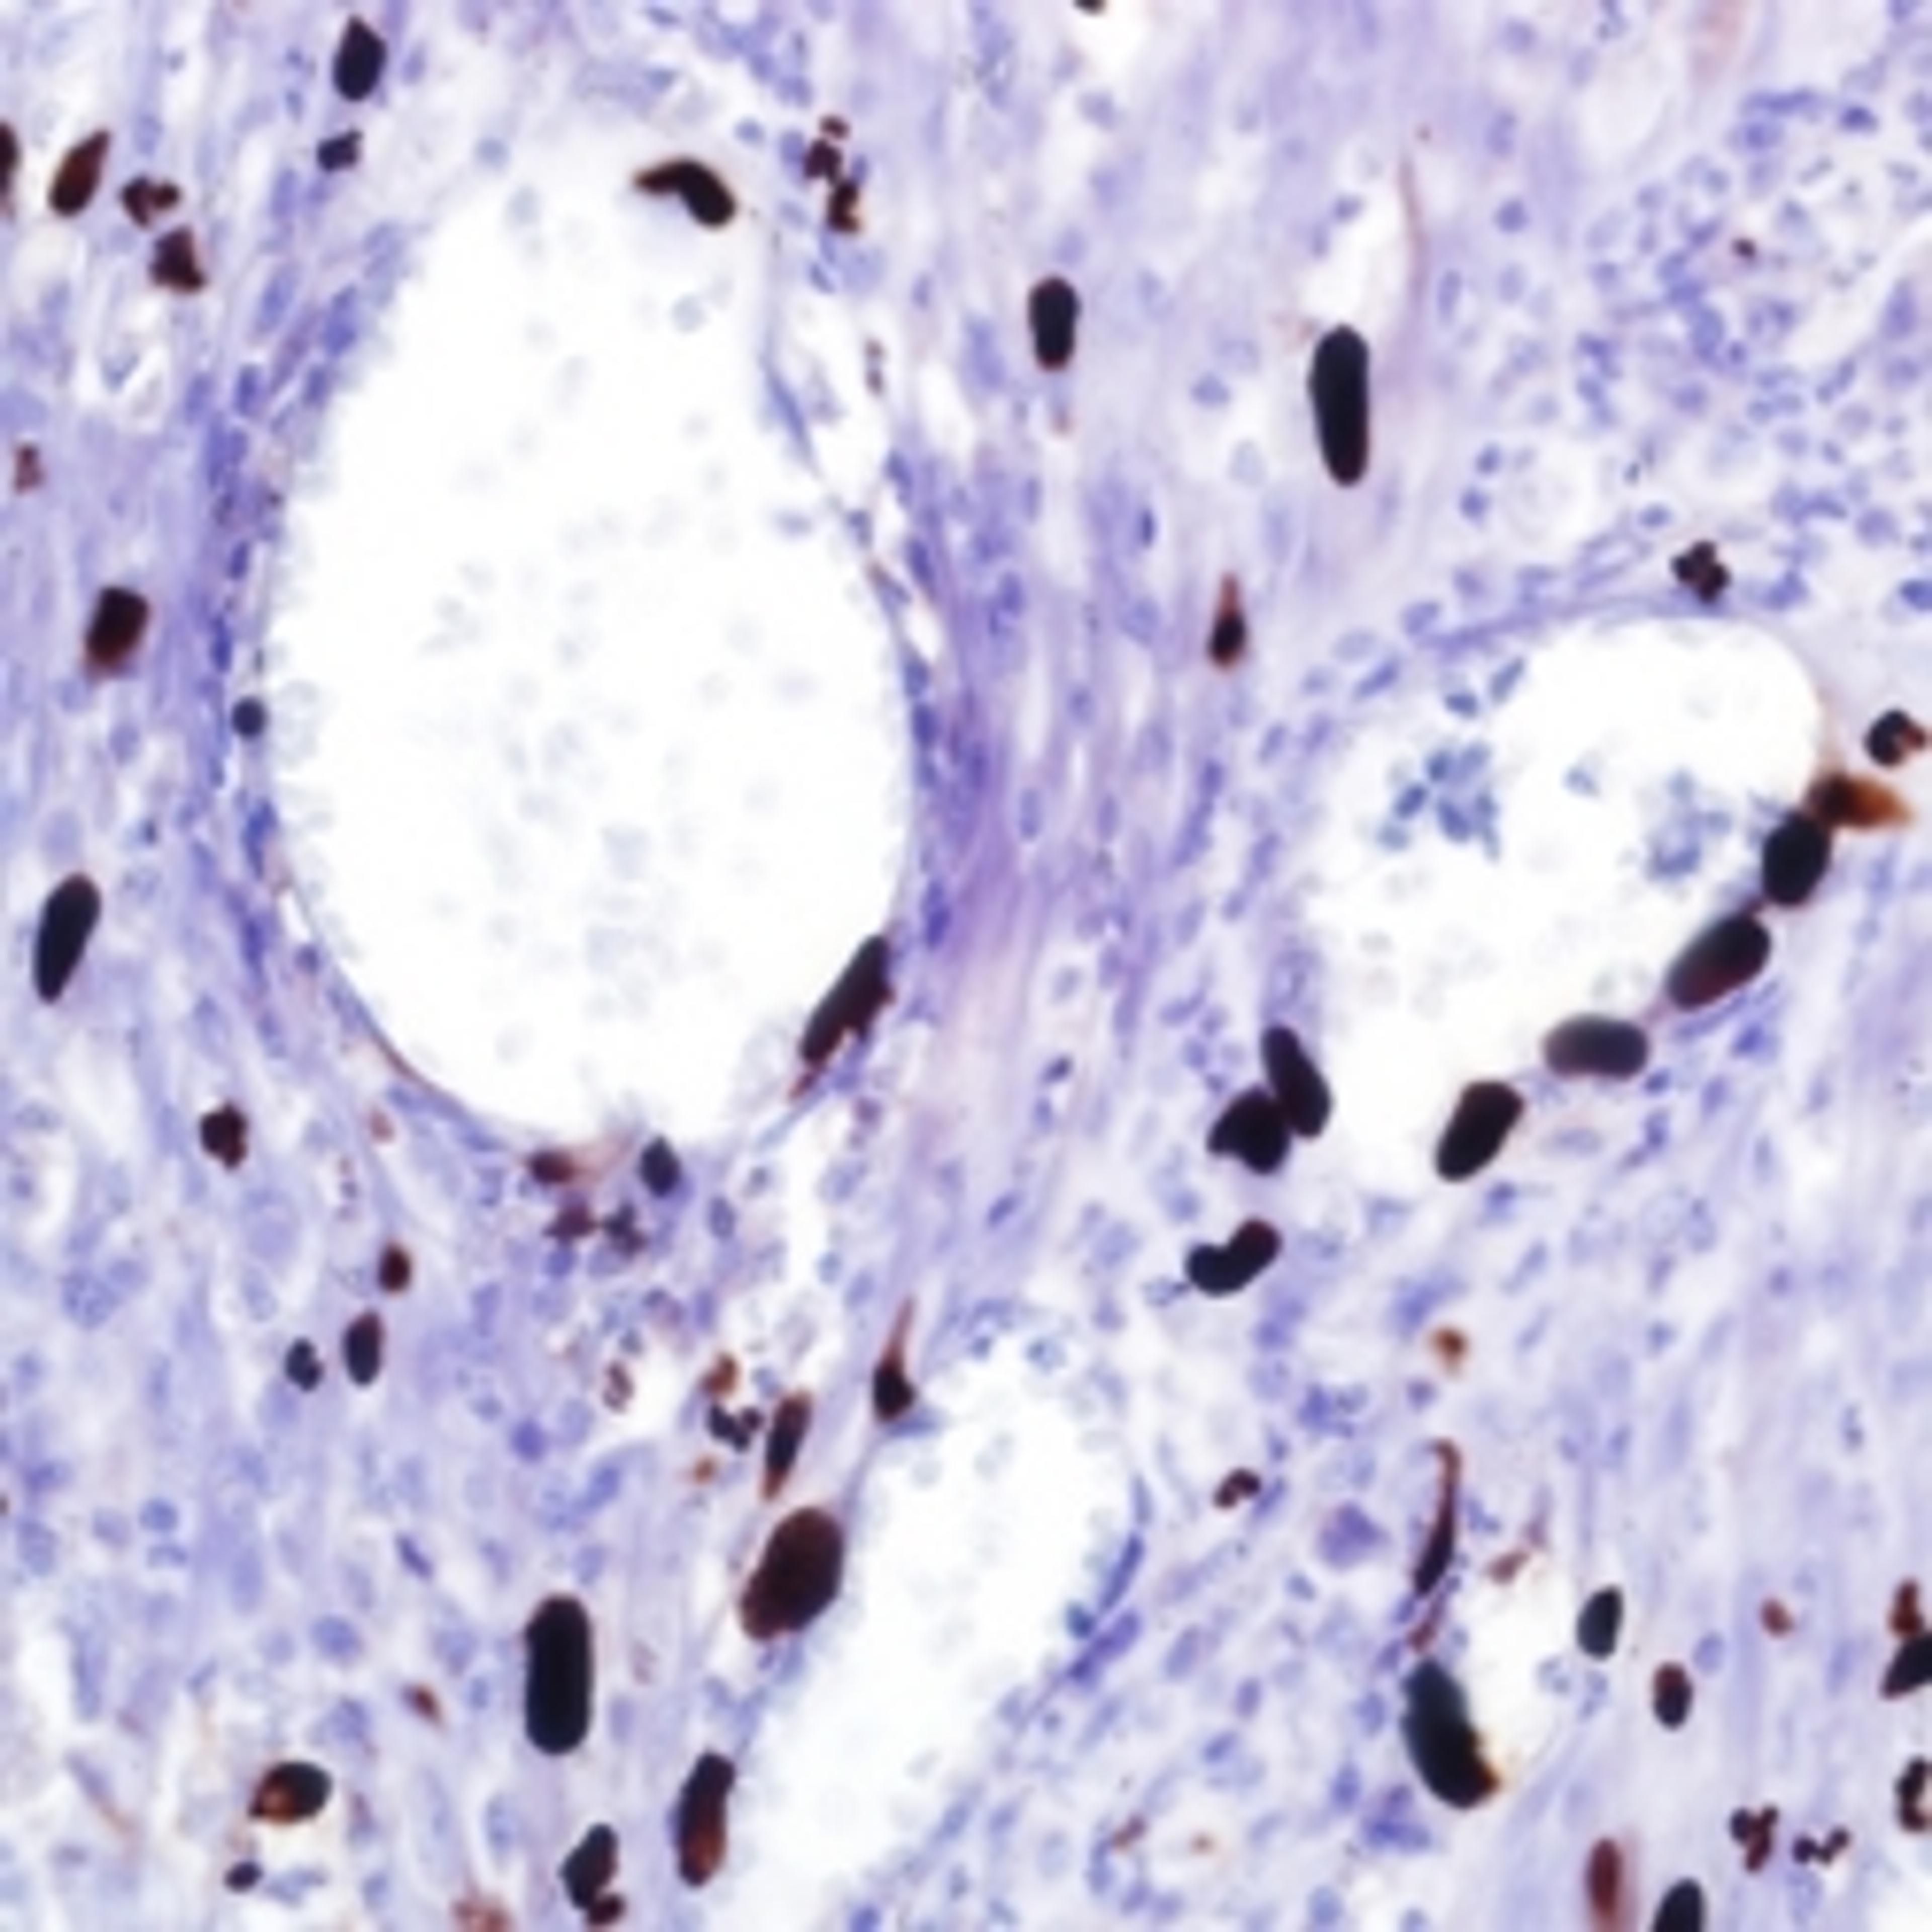

CMV (8B1.2, 1G5.2 & 2D4.2)